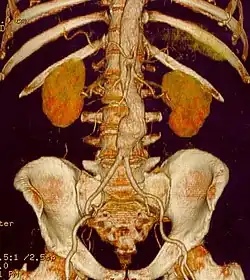

W rozpoznaniu wykonuje się badania obrazowe. Rtg klatki piersiowej, USG, tomografia komputerowa (TK), rezonans magnetyczny (MRT) są badaniami z wyboru. Stosowana jest również angiografia[1].